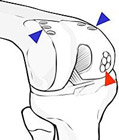

- mosaico-plastica: è una tecnica che prevede il prelievo di cilindretti di cartilagine e osso da una zona di non carico (frecce blu) del ginocchio del paziente stesso affetto da lesioni condrali focali e il loro impianto “a mosaico” nella zona di lesione (freccia rossa)